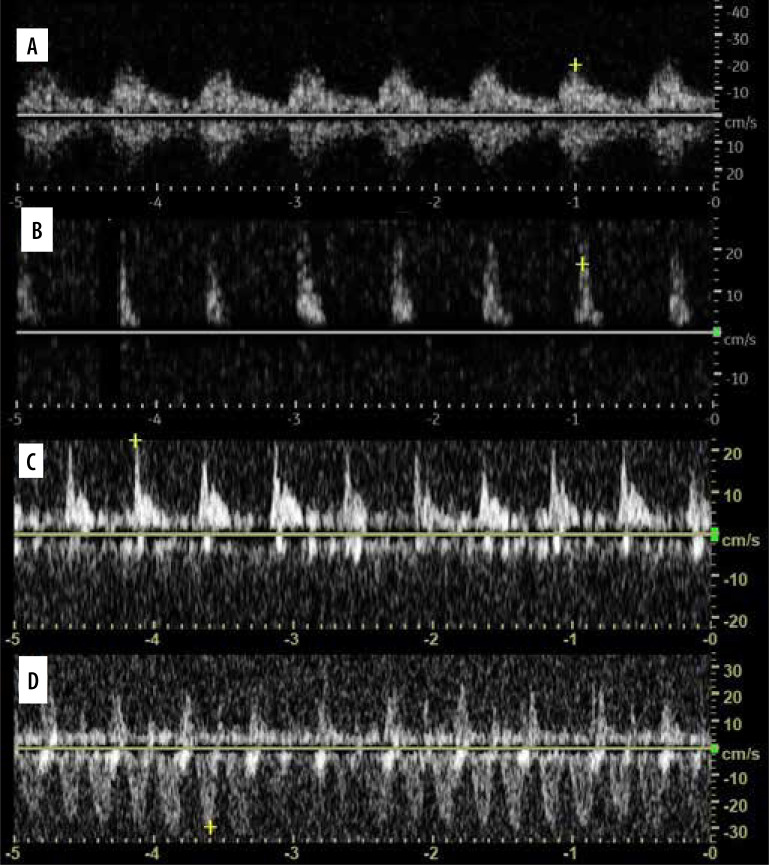

In recent years, lung ultrasound (LUS) has developed rapidly, and it is gaining growing popularity in various scenarios. There are constant attempts to introduce it to new fields. In addition, knowledge regarding lung and LUS has been augmented by the recent COVID-19 pandemics. In the first part of this review we discuss lines, signs and pheno-mena, profiles, some applications, and misconceptions. An aim of the second part of the review is mainly to discuss some advanced applications of LUS, including lung elastography, lung spectroscopy, colour and spectral Doppler, contrast-enhanced ultrasound of lung, speckled tracking of pleura, quantification of pulmonary oedema, predicting success of talc pleurodesis, asthma exacerbations, detecting chest wall invasion by tumours, lung biopsy, estimating pleural effusion volume, and predicting mechanical ventilatory weaning outcome. For this purpose, we reviewed literature concerning LUS.